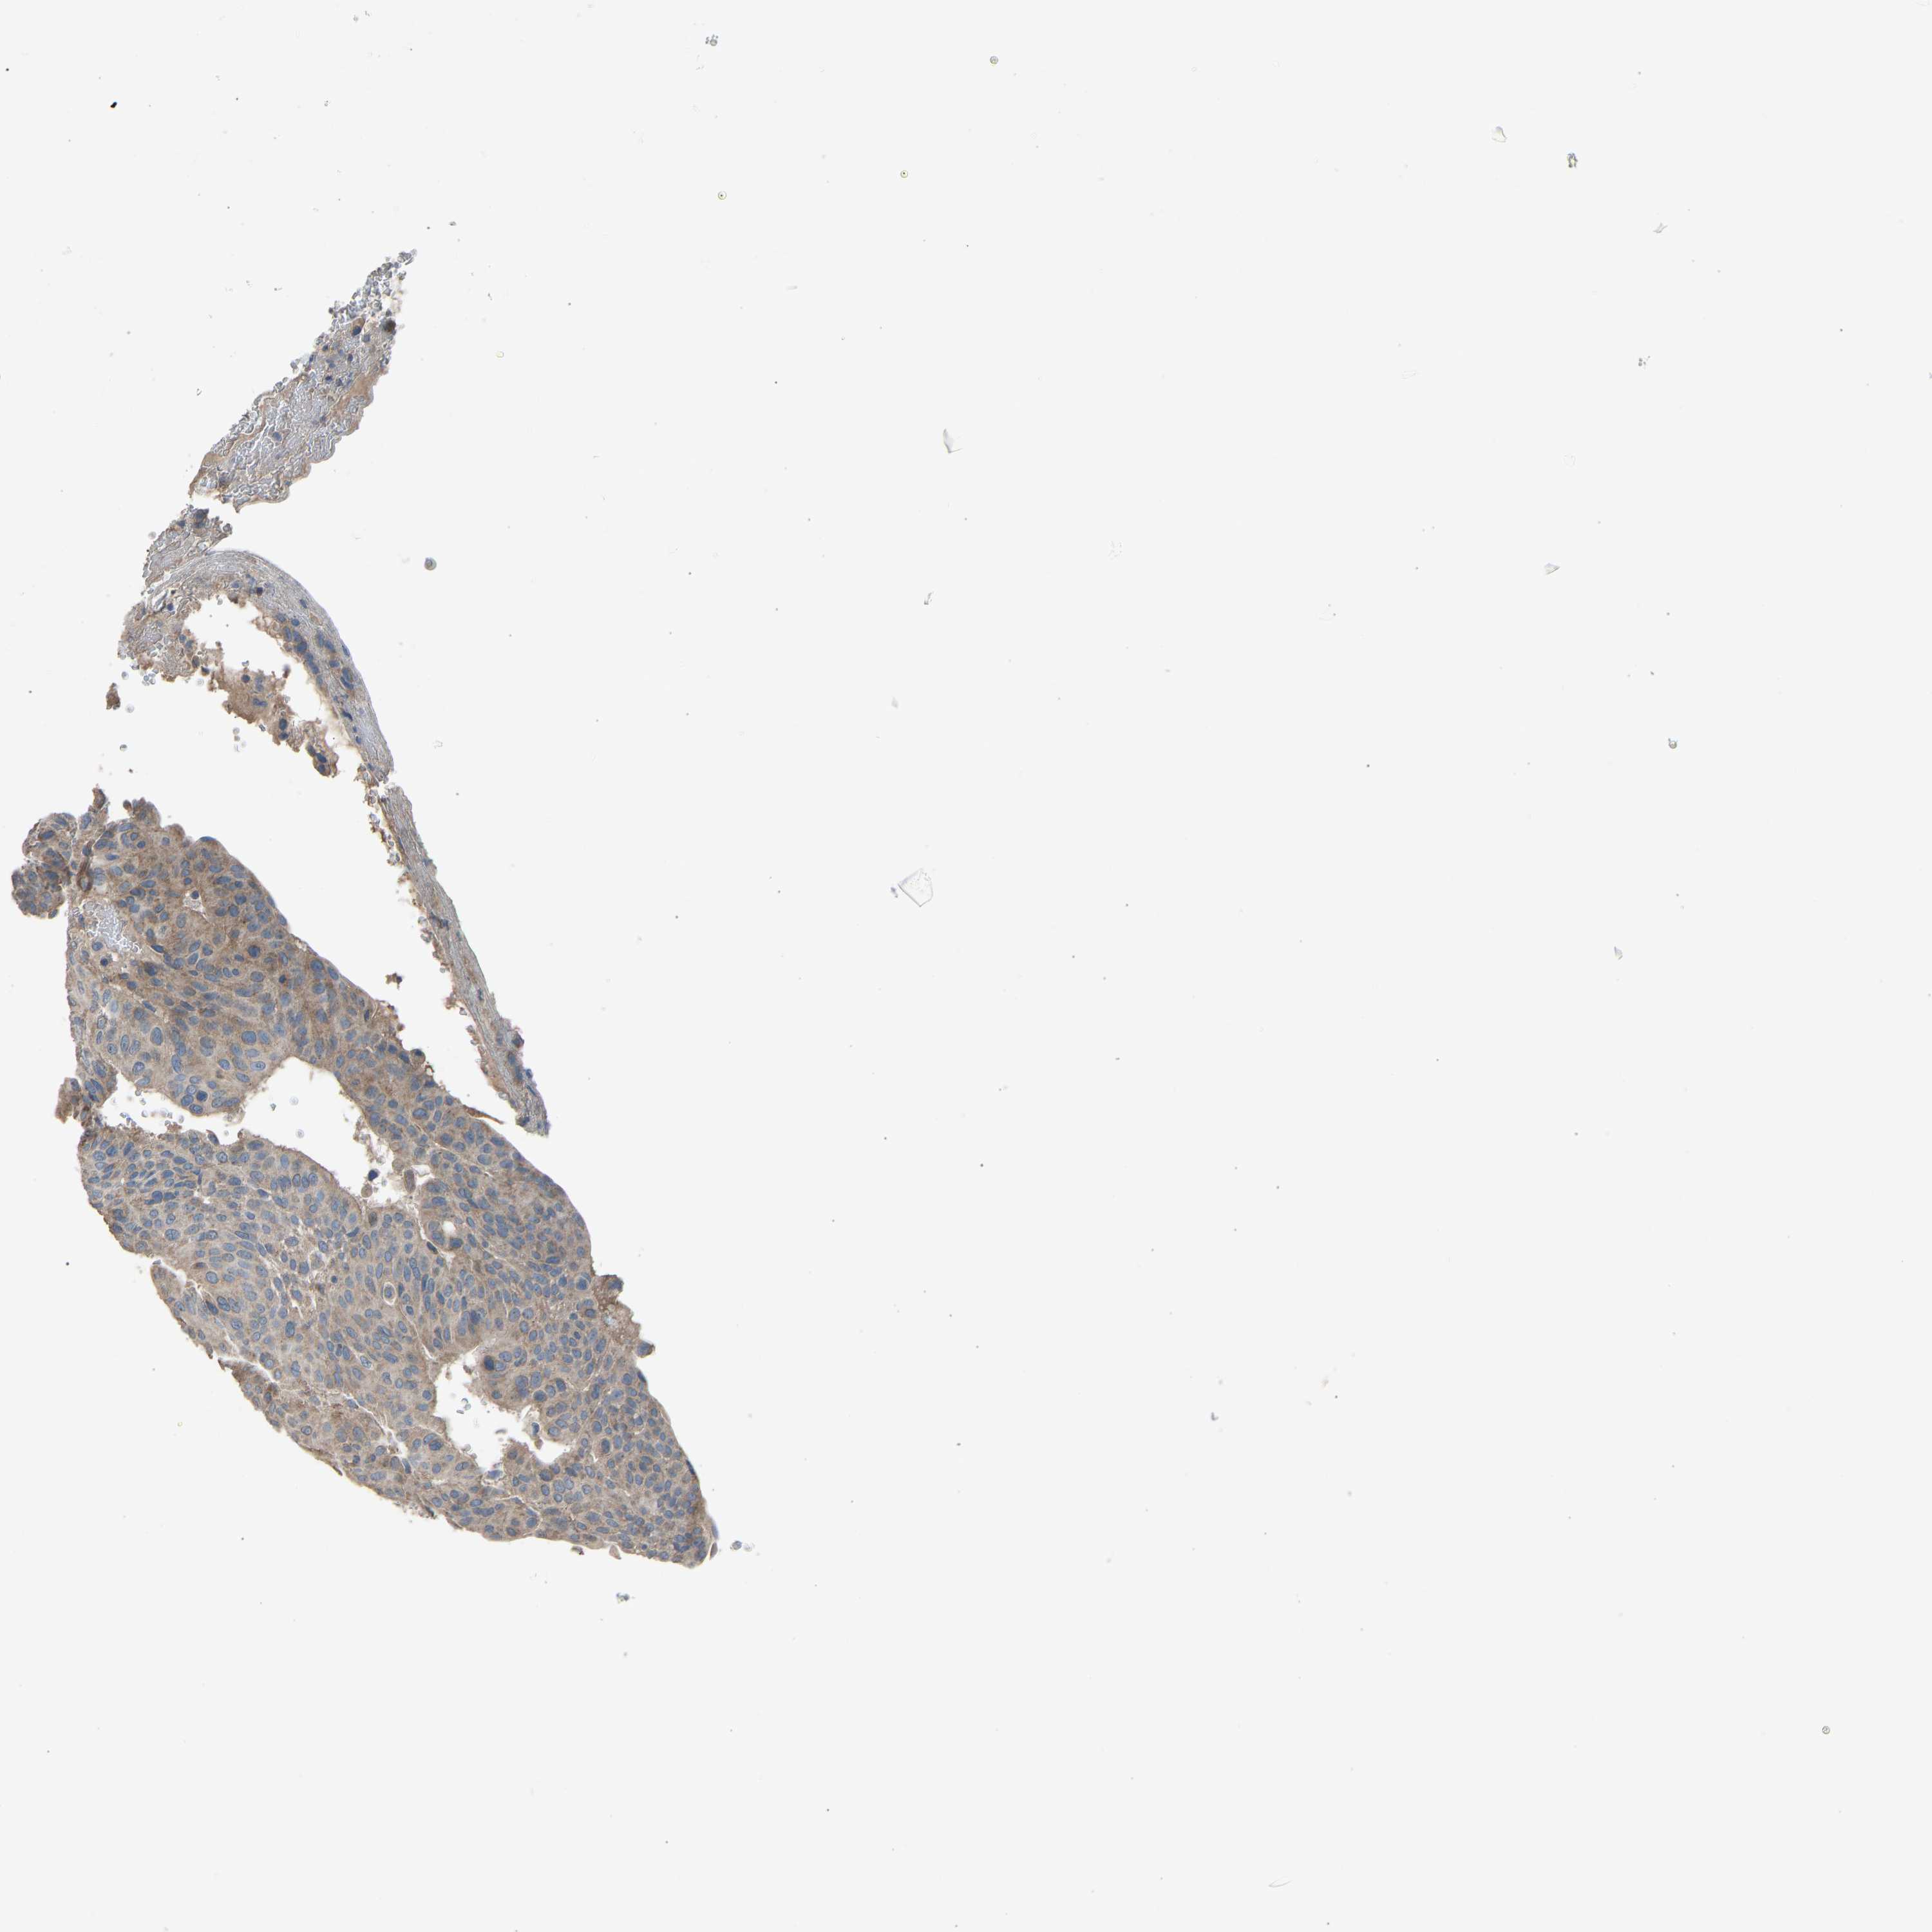

UROTHELIAL CANCER - Protein expressioni

A mouse-over function shows sample information and annotation data. Click on an image to view it in a full screen mode. Samples can be filtered based on level of antibody staining by selecting one or several of the following categories: high, medium, low and not detected. The assay and annotation is described here.

Antibody stainingi

Antibody staining in the annotated cell types in the current human tissue is reported as not detected, low, medium, or high, based on conventional immunohistochemistry profiling in selected tissues. This score is based on the combination of the staining intensity and fraction of stained cells.

Each image is clickable and will lead to virtual microscopy that enables deeper exploration of all samples and also displays staining intensity scores, fraction scores and subcellular localization as well as patient and tissue information for each sample.

Antibody HPA008257

Antibody CAB018971

Urothelial carcinoma, Low grade

Urothelial carcinoma, High grade